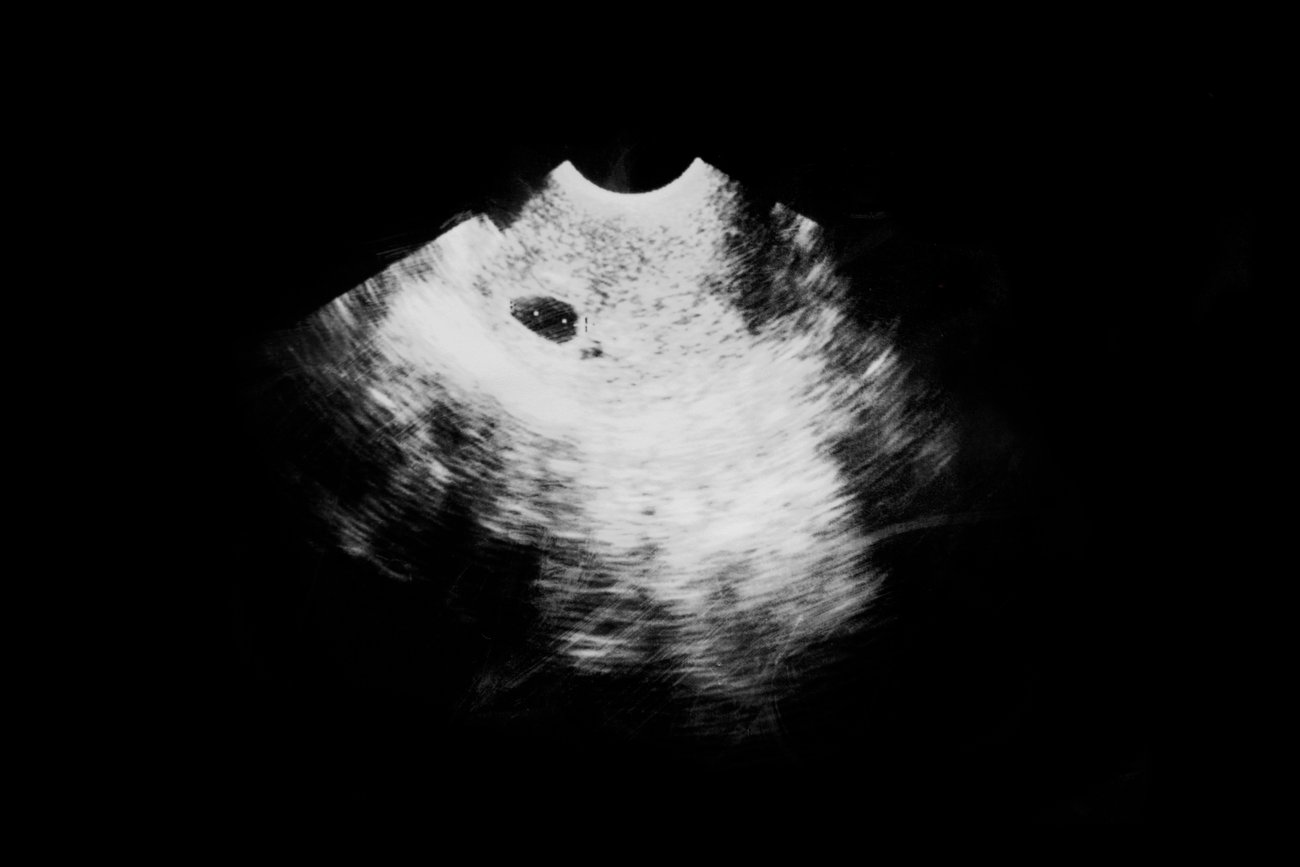

Erfahren Sie, ab wann man die Schwangerschaft im Ultraschall sieht und wie Ultraschall funktioniert Dieser ermöglicht es, das ungeborene Baby zu sehen und seine Entwicklung zu verfolgen

Wann Erste Ultraschalluntersuchung Galerien Changs Online. Erfahren Sie, ab wann man die Schwangerschaft im Ultraschall sieht und wie Ultraschall funktioniert Schwangerschaftswoche, wenn der Embryo erst wenige Millimeter gross ist, liefert die Vaginalsonografie bessere und kontrastreichere Bilder als ein Ultraschall über die Bauchdecke.